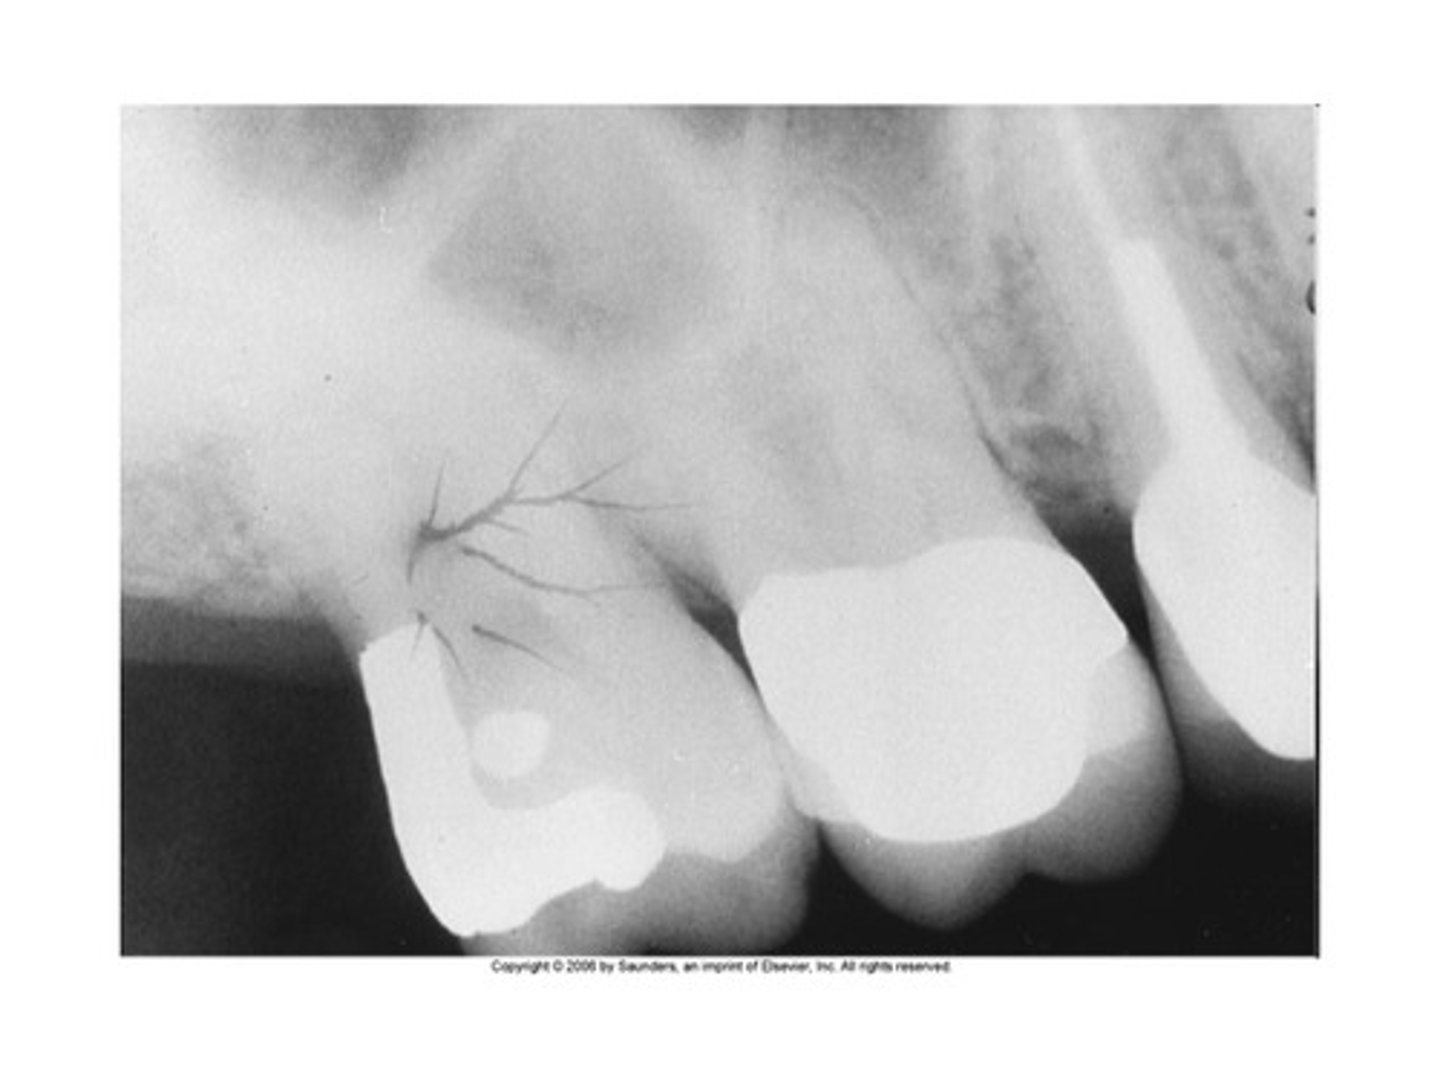

Phalangioma

Distal phalanx of the finger is seen in the radiograph

<p>Distal phalanx of the finger is seen in the radiograph</p>